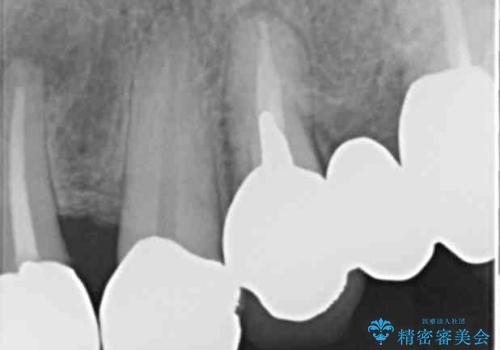

- 前歯のセラミック治療から4年半経過した患者様です。

4年ぶりに来院して下さいました。

治療した上の前歯6本は全く問題なく、「獅子舞みたいだった前歯を綺麗にして下さってありがとうございました!」と再度お礼を言って下さいました。

4年半前のクラウン装着時と変わらず、まるで天然歯のように自然に見えました。

患者様の良好なセルフケアと精密な適合の良いクラウンにより、歯肉の腫脹や退縮も認められませんでした。

4年半前に行った治療に大変ご満足頂き、他の部位の治療のため再来院して下さいました。